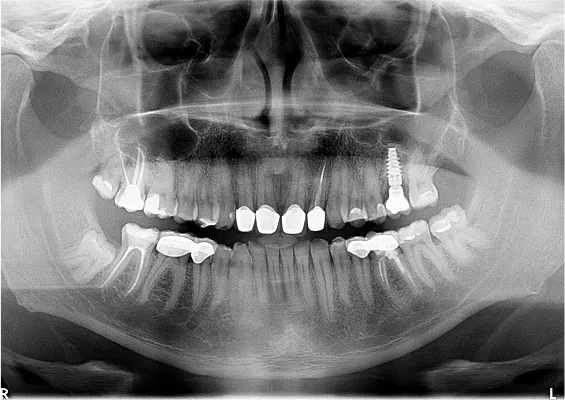

ZABIEGI REGENERACJI KOSTNEJ WOKÓŁ WSZCZEPIANYCH IMPLANTÓW

Sterowana regeneracja kości GBR przy użyciu biomateriałów oraz membran zaporowych. Procedury te są stosowane w sytuacji niedostatecznej ilości kości, skutkującej odsłonięciem gwintu, podczas gdy wszczepiamy implanty stomatolo-giczne lub też jako zabiegi poprzedzające ich wprowadzenie.